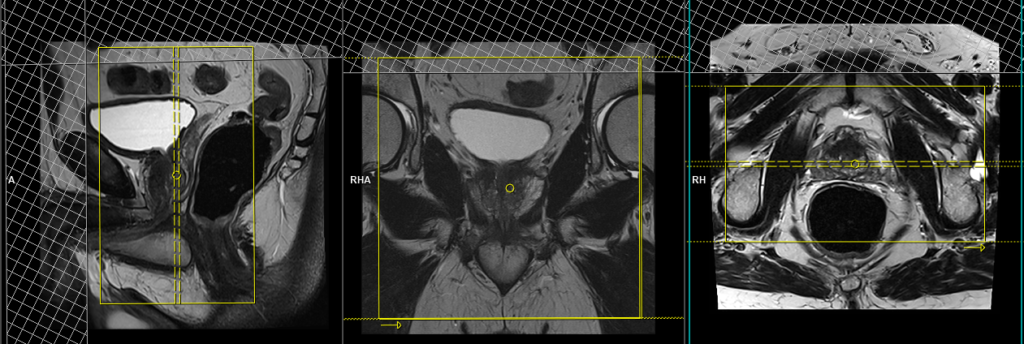

ZOOMIT DWI \ epi 4 scan trace axial 3 mm SFOV b50_b500_b800_1400

Plan the axial DWI block on the sagittal plane; angle the positioning block horizontally across the prostate (i.e., parallel to the base of the penis). Check the positioning block in the other two planes. An appropriate angle must be given in the coronal plane (parallel to the right and left femoral heads). Slices must be sufficient to cover the whole prostate and seminal vesicles. Additionally, to minimize artifacts arising from arterial pulsation, peristalsis, and breathing, consider incorporating saturation bands on top and in front of the axial block.

Parameters ZOOIT

TR 5000-6000 | TE 74 | FLIP 130 | NEX 10 | SLICE 3 MM | MATRIX 204X192 | FOV 200X110 | PHASE R>L | NSA 3 4 5 9 | B VALUE 0 |

Parameters EPI DWI

TR 5000-6000 | TE 110 | FLIP 130 | NEX 10 | SLICE 3 MM | MATRIX 192X192 | FOV 200-250 | PHASE R>L | NSA 3 4 5 9 | B VALUE 0 |